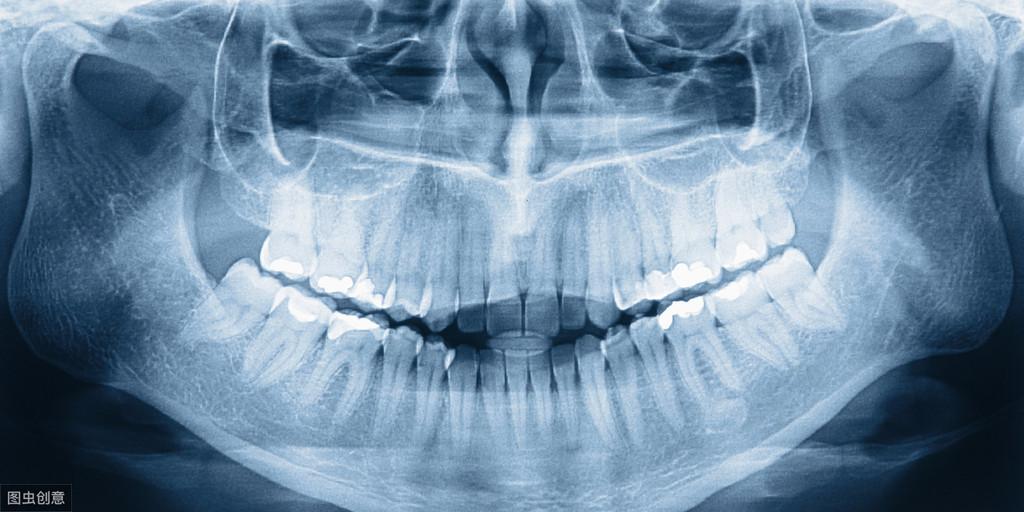

病情分析:牙齒矯正只能矯正牙列不齊,不能調(diào)節(jié)氟斑牙。如果是傳統(tǒng)的直絲弓矯正器,費用一般是1-2.5萬,如果是隱形矯正,需要2-6萬左右。具體要看地區(qū)和選擇的托槽。

牙齒如果有牙列的擁擠,有牙裂不齊,有中線的偏移或者是有牙縫,或者是有齙牙,或者是有地包天,或者是有開頜等等,都是需要做牙齒的矯正調(diào)節(jié)的。牙齒矯正的費用,不同的地區(qū)費用有所不同,而且不同的矯正方法費用也有所不同,不同的材料費用也有所不同。一般來說,如果是金屬托槽矯正,那么費用在15000到18000之間。如果是自鎖托槽矯正,那么費用在兩萬左右。如果是隱形矯正,那么費用大概是在4萬到5萬元左右,所以說牙齒矯正的價格是有所不同的。很多患者如果有牙齒的錯頜畸形,不管費用有多高,我們還是需要做矯正的,否則就有可能造成很多的并發(fā)癥。。